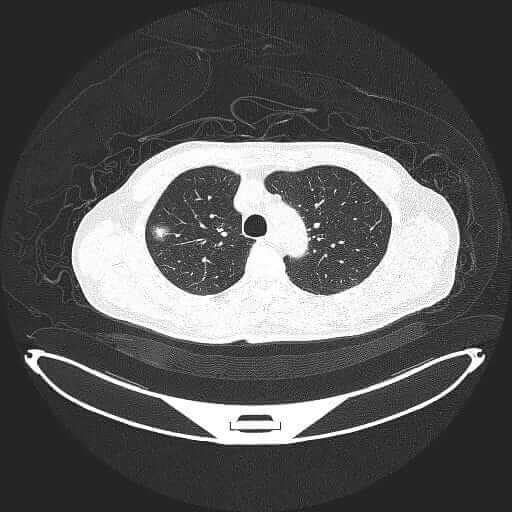

悪性リンパ腫 多発性リンパ節転移 左肺下葉腫瘍

原因不明がん/多発性リンパ節転移/左肺下葉腫瘍画像